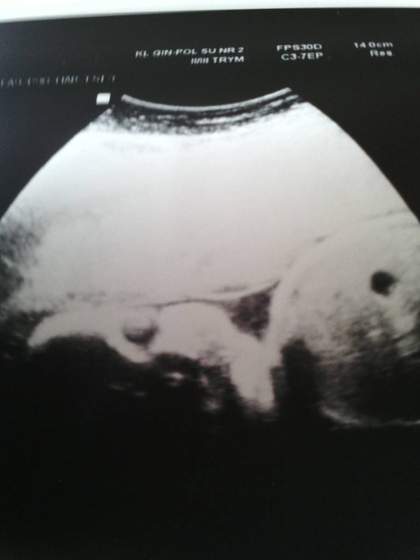

a niunia na was patrzy ;)

Załączniki

• 1422524426492.jpg

1422524426492.jpg

11,8 KB · Wyświetleń: 68